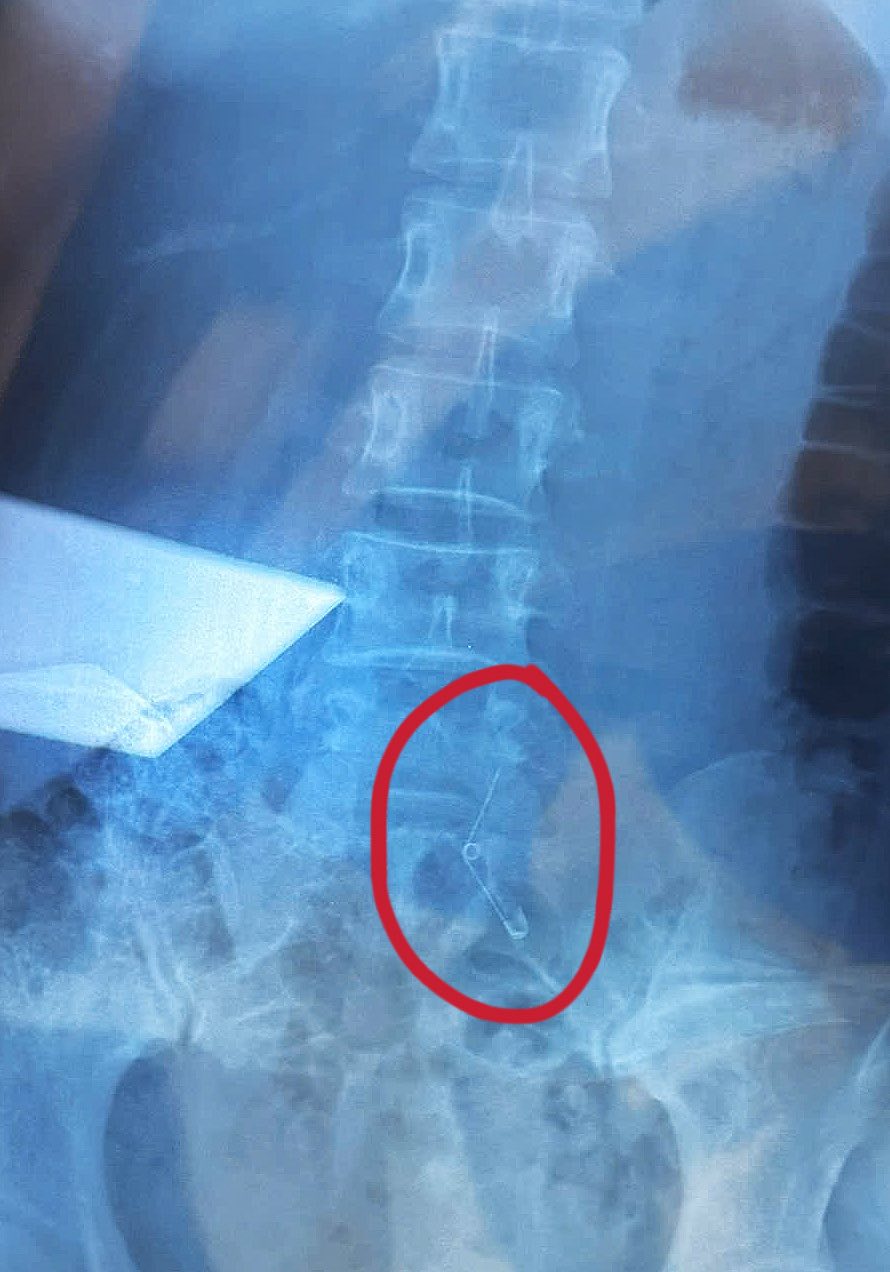

Theo chia sẻ, lúc ăn cô thấy nghẹn nghẹn nhưng vẫn ăn uống bình thường, khi ăn xong mới vào viện kiểm tra, chụp X-quang và phát hiện vật thể lạ trong bụng. Vì không nội soi thực quản được nên cô phải mổ dạ dày, mất 6 tiếng trong phòng mổ.

Cận cảnh chiếc kim băng từ lúc trên bàn ăn, khi đã nuốt vào bụng và lúc được phẫu thuật lấy ra

Chỉ nhớ là cắm cái món răng mực - nuốt xong nhìn xuống tay không thấy kim nữa! Tìm xung quanh không thấy vẫn ngồi ăn tiếp đến khuya mới vào viện chụp thử ai ngờ nó sắp chui xuống ruột rồi. Ảo thật đấy!” - nguyên văn chia sẻ mới của Vân Anh trên trang cá nhân.